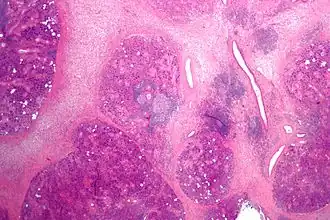

Расширение протока с задержкой слюноотделения, гроздевидная атрофия или утолщённая и отёчная слизистая оболочка, гнойный или серозно-гнойный экссудат внутри протока, замещение железистой ткани фиброзной, инфильтрация лейкоцитами.